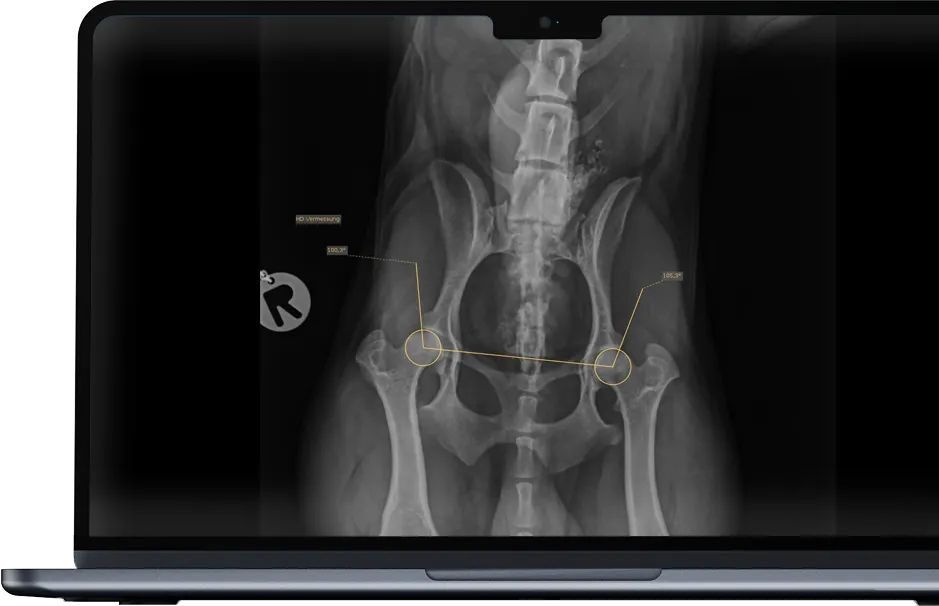

Pantalla táctil de 24″, software de rayos X integrado, funciones de medición asistidas por IA, mesa flotante de 4 vías, visualización del flujo de trabajo en 3 colores

dicomPACS®DX-R es el corazón de nuestros sistemas OR 4Vet: con manejo inteligente, soporte de IA, radiografía dinámica y control inalámbrico, perfectamente adaptado a la medicina veterinaria moderna. Un software de adquisición y diagnóstico rápido y fiable que le apoya de manera óptima en la práctica diaria.